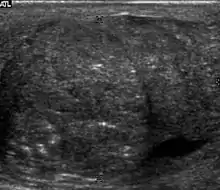

Seminoma is the most common tumor type in cryptorchid testes. The risk of developing a seminoma is increased in patients with cryptorchidism, even after orchiopexy. There is an increased incidence of malignancy developing in the contralateral testis too, hence sonography is sometimes used to screen for an occult tumor in the remaining testis. On US images, seminomas are generally uniformly hypoechoic, larger tumors may be more heterogeneous [Fig. 3]. Seminomas are usually confined by the tunica albuginea and rarely extend to peritesticular structures. Lymphatic spread to retroperitoneal lymph nodes and hematogenous metastases to lung, brain, or both are evident in about 25% of patients at the time of presentation.

Patients with testicular lymphoma are usually old aged around 60 years of age, present with painless testicular enlargement and less commonly with other systemic symptoms such as weight loss, anorexia, fever and weakness. Bilateral testicle involvements are common and occur in 8.5% to 18% of cases. At sonography, most lymphomas are homogeneous and diffusely replace the testis [Fig. 7]. However focal hypoechoic lesions can occur, hemorrhage and necrosis are rare. At times, the sonographic appearance of lymphoma is indistinguishable from that of the germ cell tumors [Fig. 8], then the patient's age at presentation, symptoms, and medical history, as well as multiplicity and bilaterality of the lesions, are all important factors in making the appropriate diagnosis.